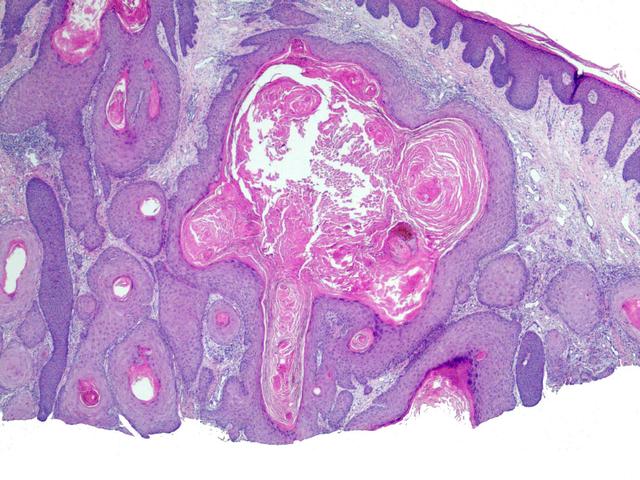

结直肠癌:通过结直肠镜、DNA、FIT早筛。高危人群包括50岁以上,有肠息肉病家族史,爱吃高脂、高热量食物,抽烟酗酒,患有结肠腺瘤综合征、慢性溃疡性结肠炎、肠血吸虫肉芽肿等等。